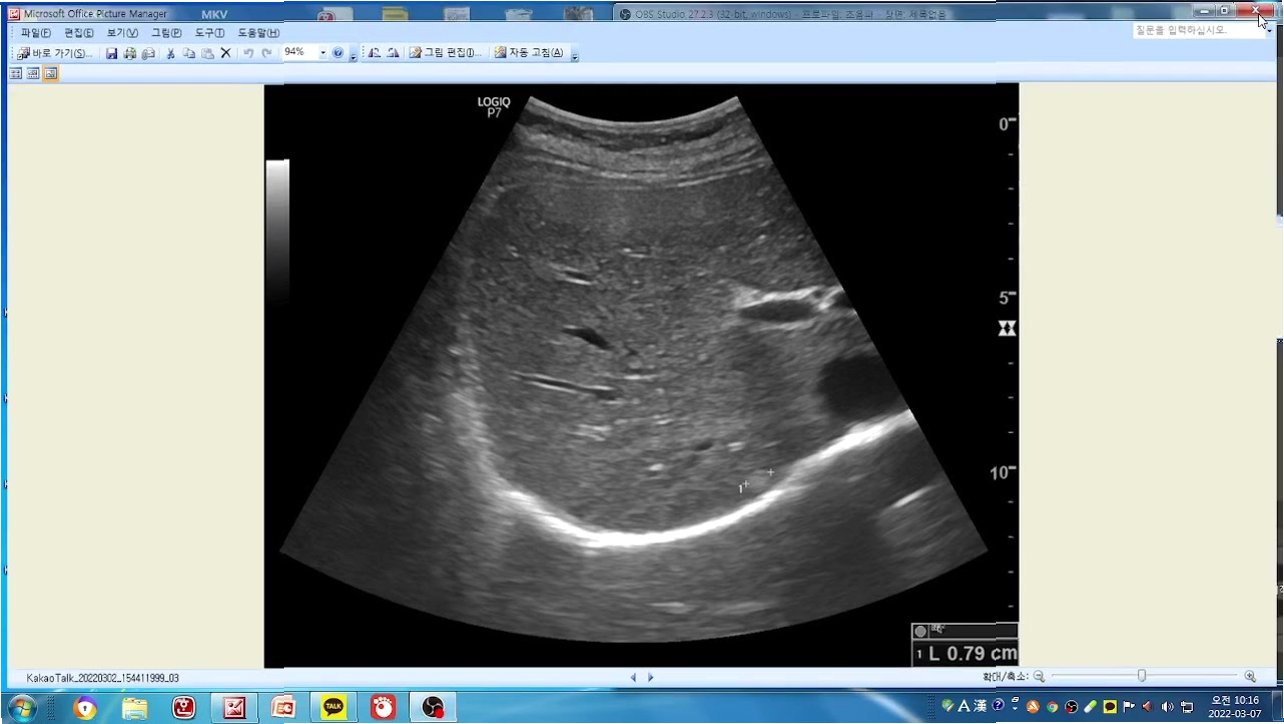

S.E.S. 출신 슈가 SBS '스타건강랭킹 넘버원'에서 간혈관종 진단을 받아 많은 이들에게 충격을 안겨주고 있습니다. 10일 방송 예고를 통해 슈의 건강 상태가 공개되었는데요, 뱃살은 찾아볼 수 없지만, 예상치 못한 건강 문제로 팬들의 걱정을 자아냈습니다. 슈는 평소 소화불량과 변비로 고생했다고 밝혔으며, 극심한 변비로 응급실을 찾았던 경험도 털어놓았습니다. 이번 방송에서는 슈의 건강 검진 결과를 통해 간에서 종양이 발견되었고, 전문가는 이를 '간혈관종'으로 진단했습니다. 슈는 뜻밖의 진단에 당혹감을 감추지 못했습니다. 이번 소식을 통해 건강 관리에 대한 중요성을 다시 한번 깨닫게 됩니다.

간혈관종, 무엇이 문제일까?

간혈관종은 간에 발생하는 양성 종양으로, 대부분 무증상으로 발견되는 경우가 많습니다. 하지만 크기가 커지거나 다른 문제를 일으킬 경우, 복통, 팽만감 등의 증상을 유발할 수 있습니다. 슈의 경우, 소화불량과 변비 증상이 있었던 것으로 보아, 간혈관종이 이러한 증상에 영향을 미쳤을 가능성도 있습니다. 전문의의 정확한 진단과 치료가 필요한 상황입니다. 이번 방송을 통해 간혈관종에 대한 자세한 정보와 함께 슈의 건강 회복을 위한 노력이 공개될 예정입니다. 팬들은 슈의 건강한 모습을 다시 볼 수 있기를 간절히 바랍니다.